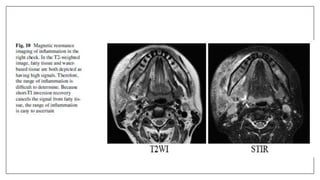

MRI in space infection

• Used in deep neck space infection: Retropharyngeal and Parapharyngeal